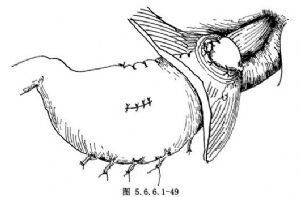

(13)食管胃吻合口周围可以用细丝线间断浆肌层褥式缝合包埋一周。将“胸胃”与食管裂孔周围的组织用细丝线间断缝合固定(图5.6.6.1-49)。